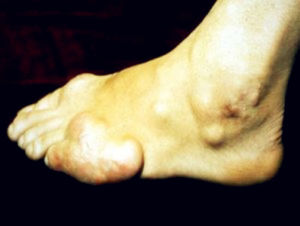

(三)痛風石及慢性關節炎

在未經治療病人,尿酸鹽在關節內沉積增多,炎症反覆發作進入慢性階段而不能完全消失,引起關節骨質侵蝕缺損及周圍組織纖維化,使關節發生僵硬畸形、活動受限,在慢性病變的基礎上仍可有急性炎症反覆發作,使病變越來越加重,畸形越來越顯著,嚴重影響關節功能。個別患者急性期症狀輕微不典型,待出現關節畸形後始被發現。少數慢性關節炎可影響全身關節包括肩髖等大關節及脊柱。此外,尿酸鹽結晶可在關節附近肌腱、腱鞘、及皮膚結締組織中沉積,形成黃白色,大小不一的隆起贅生物即所謂痛風結節(或痛風石),可小如芝麻,大如雞蛋或更大,常發生於耳輪、前臂伸面、跖趾、手指、肘部等處,但不累及肝、脾、肺及中樞神經系統。結節初起質軟,隨著纖維組織增生,質地越來越硬。在關節附近易磨損處的結節,其外表皮菲薄,容易潰破成瘺管,可有白色粉末狀尿酸鹽結晶排出,但由於尿酸鹽有制菌作用,繼發性感染較少見,瘺管周圍組織呈慢性炎症性肉芽腫,不易癒合。痛風結節的發生和病期及血尿酸鹽增高的程度有關,一般文獻報告血尿酸鹽在8mg/dl以下者,90%患者無痛風結節,而在血尿酸鹽濃度超過9mg/dl者,50%有痛風結節,病程愈長,發生痛風結節的機會愈多。發生時間較短的質軟結節在限制嘌呤飲食,套用降尿酸藥物後,可以逐漸縮小甚至消失,但發生時間長的、質硬結節,由於纖維增生不易消失。